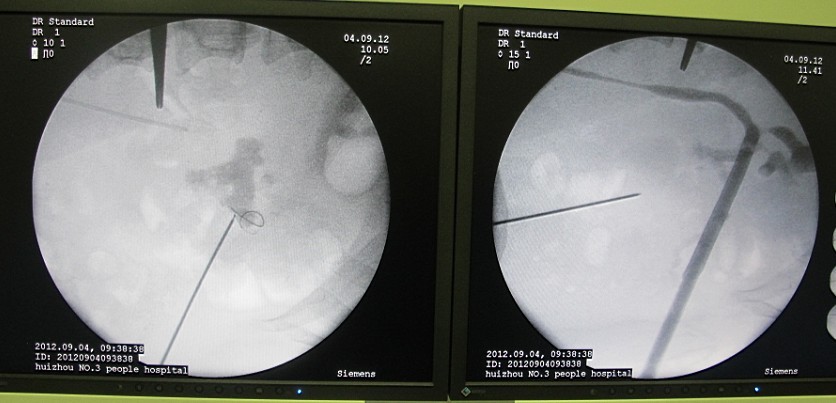

5術(shù)前和術(shù)后C臂透視可見(jiàn)通道異常精確自中小盞抵達(dá)腎盂出口。對(duì)比可以清晰的看到結(jié)石已完全清除。

6 結(jié)石沒(méi)了,置導(dǎo)絲入膀胱準(zhǔn)備放置雙J管。